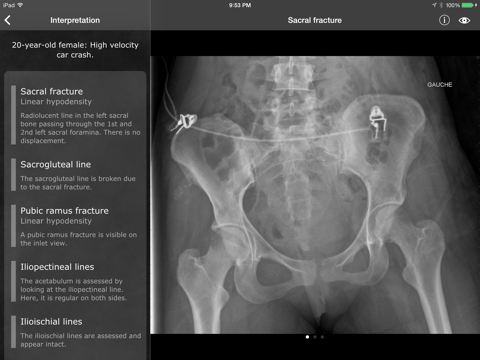

* FEATURED IN AAOS' MULTIMEDIA EDUCATION CENTER * * Now compatible with iOS 8 * RealWorld Orthopaedics is your ultimate guide to the basics of musculoskeletal medicine. This app features more than 50 chapters covering the most frequent and important diagnoses of the field, including fractures, dislocations, and degenerative diseases. The chapters are divided into sections discussing basic mechanisms of injury, diagnostic criteria and classifications, differential diagnosis as well as management. The chapters are fully illustrated using high-quality plates from Gray's Anatomy, original illustrations and original photographs. RealWorld Orthopaedics is also the best musculoskeletal radiology resource on the App Store! Not only can you see radiographs of every discussed disease, all radiologic findings can be highlighted right on the X-ray. Explore more than 150 real cases each containing: - Clinical information regarding the patient and the mechanism of injury - High-resolution X-rays - All appropriate series (anteroposterior, lateral, oblique, etc.) - Detailed radiologic interpretation - Drawings of every radiological finding right on the X-ray - Pre and postoperative controls Test your knowledge with the quiz mode, where the radiographs are presented in random order, or access a case directly either by diagnosis (e.g. Galeazzi fracture, rhumatoid artitis) or by actual radiological finding (e.g. linear hypodensity, plate and screws, irregular joint surface). By being both a radiology resource and a comprehensive clinical reference, RealWorld Orthopaedics is your must-have app for quick review on the wards, or at home. ==================================== PRAISE FOR REALWORLD ORTHOPAEDICS ==================================== "This is one of the best musculoskeletal radiology apps available. [...] Useful to any medical student, intern, or junior resident that needs to learn about musculoskeletal radiology." - TopOrthoApps.com "Highly rated orthopaedic application" - Orthopaedia.com "The ultimate iPhone app to the learning of musculoskeletal radiology" - echo-loco.fr Featured in AAOS' Multimedia Education Center (San-Francisco 2012) Featured by Apple as "New and Noteworthy" in more than 50 countries worldwide. ========================= INTERNATIONAL USER REVIEWS ========================= Great ortho app - 5 stars by miwwiw - Version 2.0.0 - Mar 21, 2012 - Australia iTunes Store Very easy to use app, best ortho app in the apple store. Great for anyone on a orthopaedic surg attachment wanting a good source of X-rays along with highlights of abnormalities plus full explanations & background info. [...] Definitely worth the $$, looking forward to future updates. --- Excellent for consenting - 5 stars by Drpsy23 - Version 2.0.0 - Apr 21, 2012 - UK iTunes Store I use this app a lot in order to inform and explain procedures to patients, Excellent to calm the anxiety of parents!!!! --- A compact, high quality atlas of skeletal radiological appearances - 5 stars by jepho - Version 1.0.0 - 31 March 2011 - UK iTunes Store A fantastic job! This is a great reference work for anyone interested in seeing real examples of diagnostic imaging for skeletal trauma and disease. The viewer is a joy to use [...] I have no hesitation in recommending this application very highly. [...] It will probably replace my battered copy of Orthopaedic Radiology (Long and Rafert) [...] This seminal work deserves to be on every clinician's iPhone. At this minimal cost, they have no excuse for not purchasing this application. I predict that it will become a classic. --- Muy buena - 5 stars by Unpg - Version 2.0.0 - Feb 24, 2012 - Spain iTunes Store Excelente y necesaria para traumas